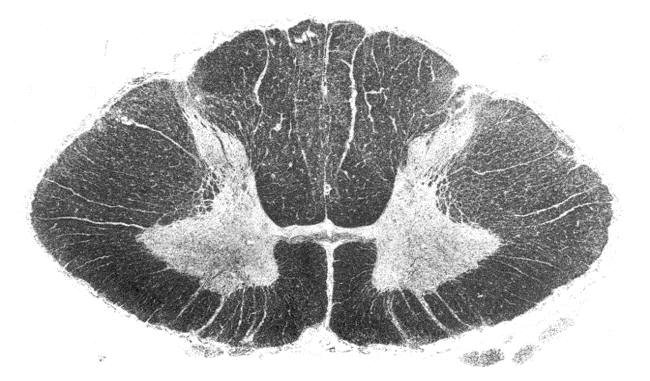

spinal cord. dorsal horn grey matter at the top half and ventral at the bottom